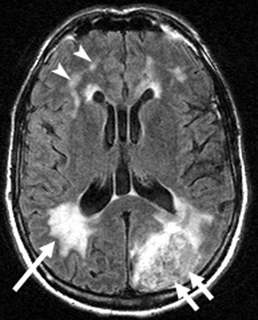

- MRI Brain image from the web - arrows identify white matter hyperintensities